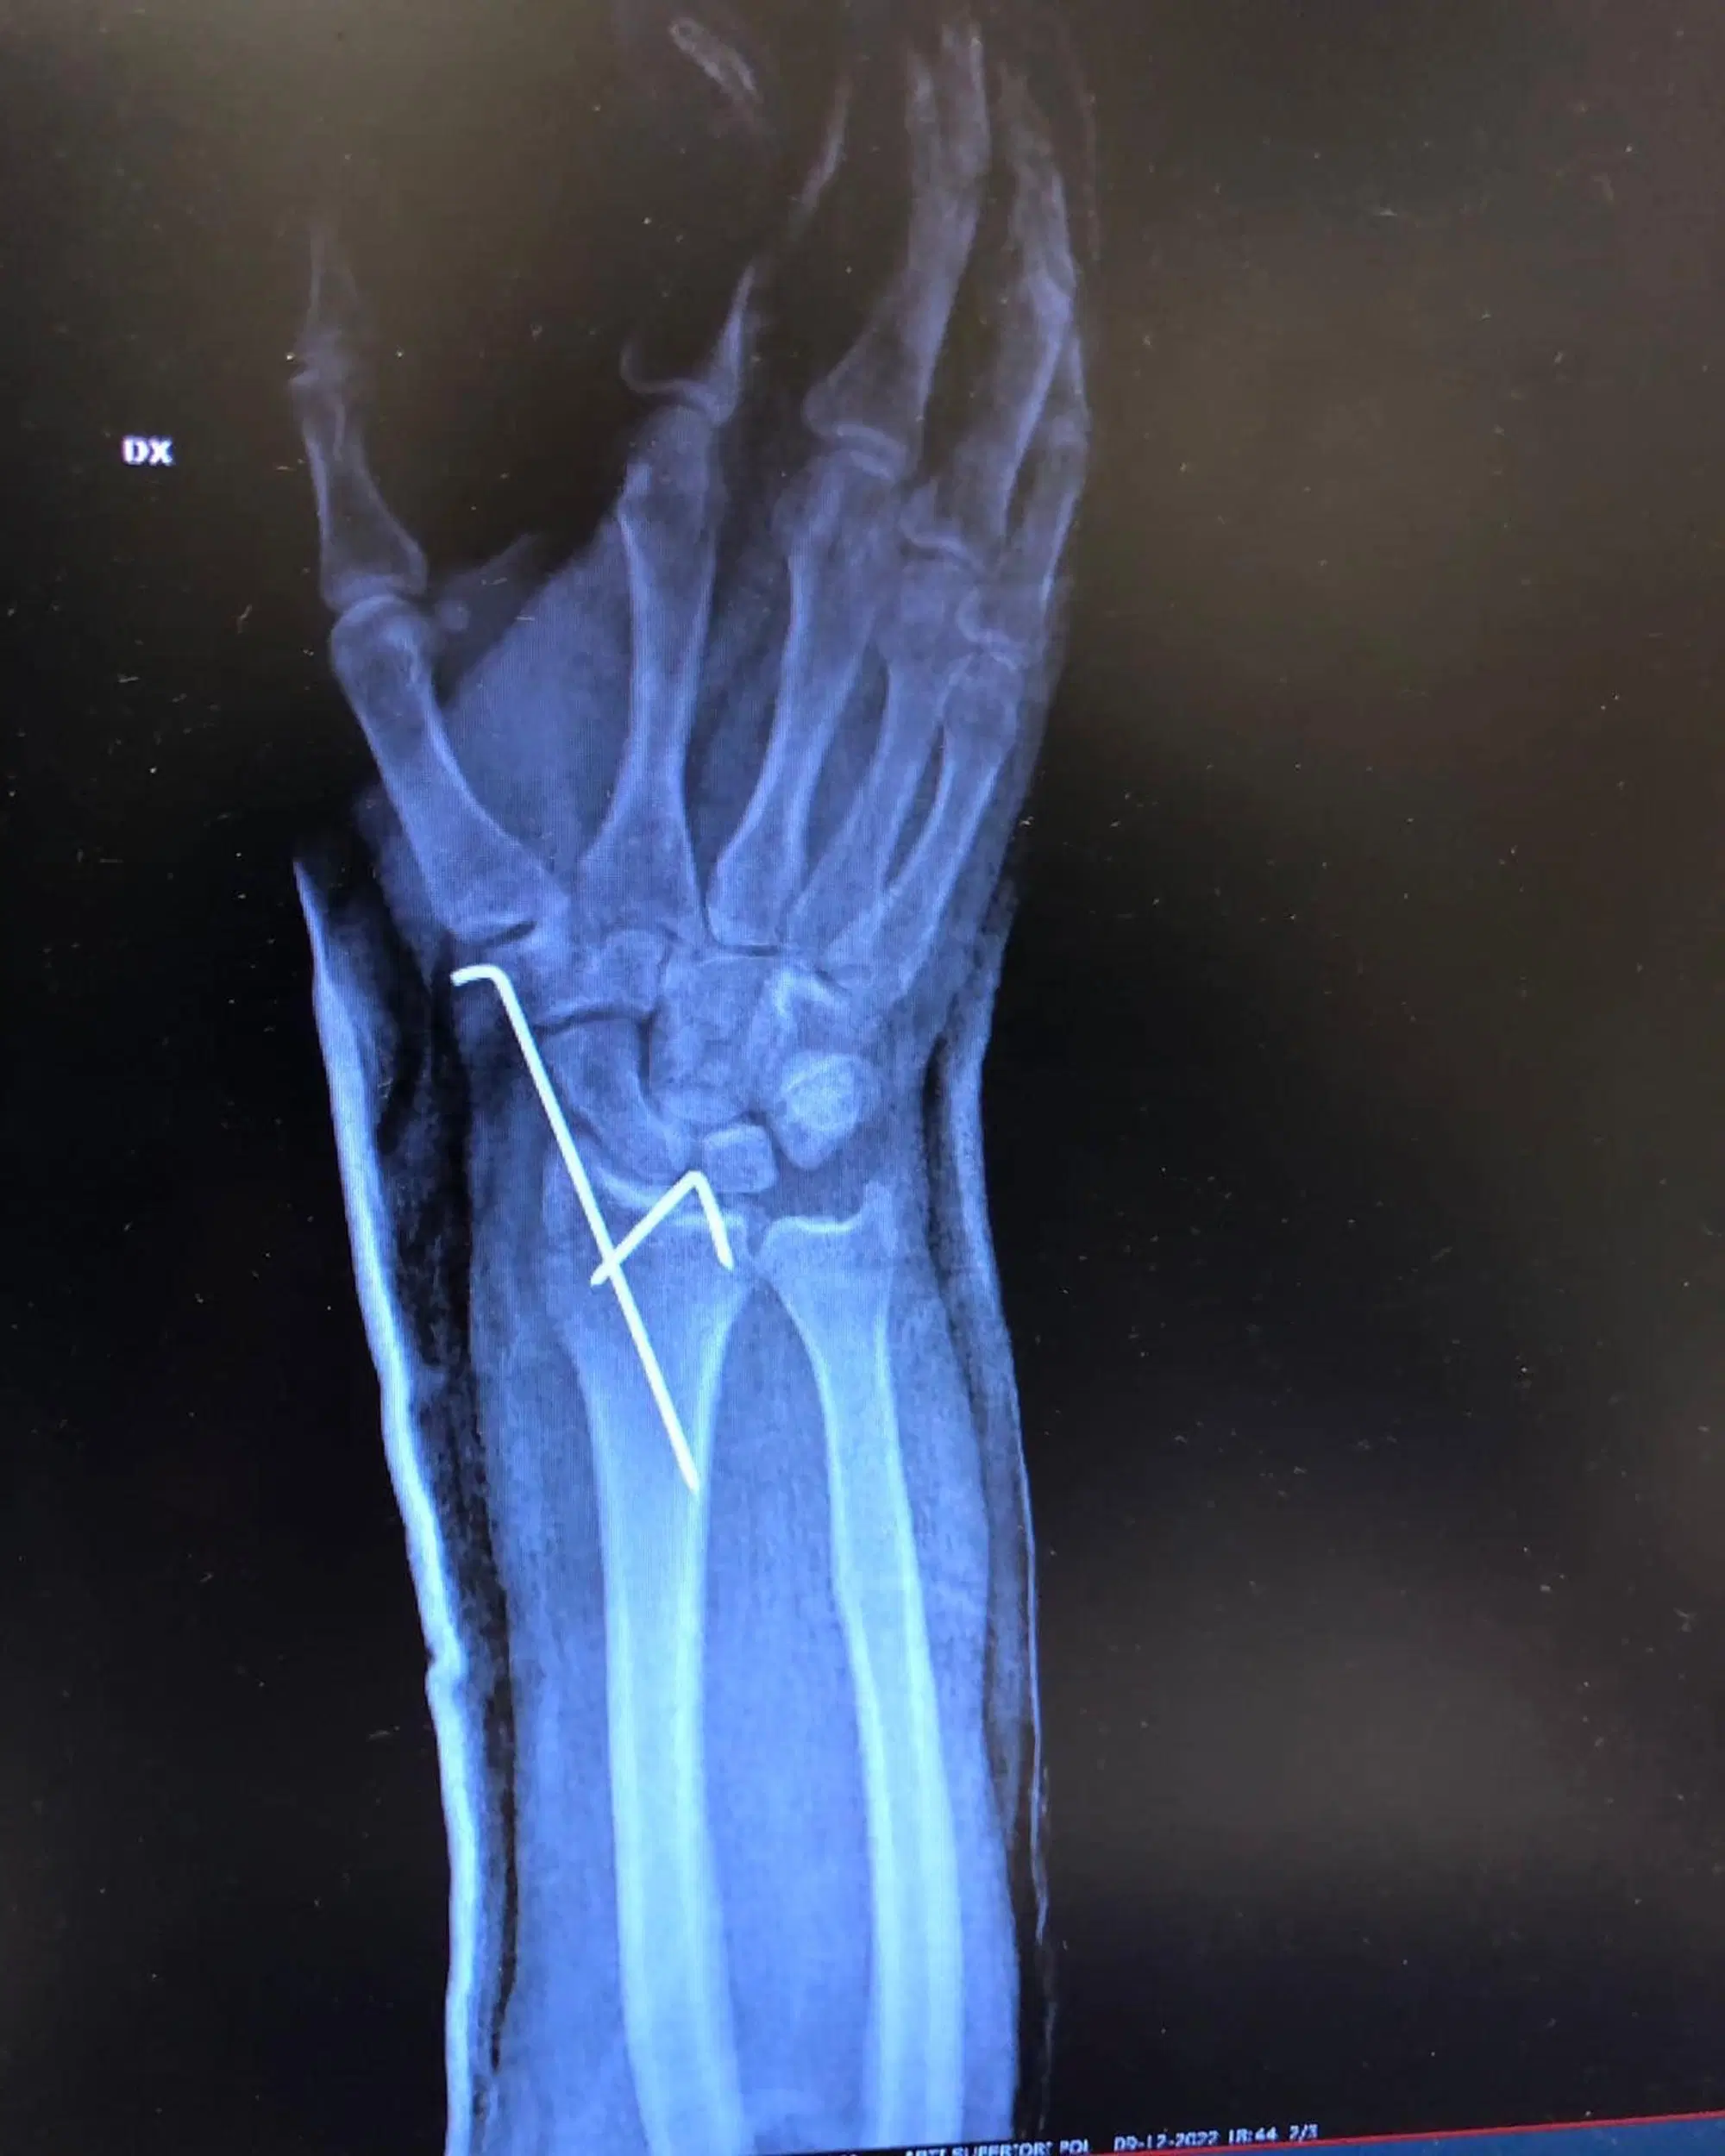

"C'è questa nuova moda che i crossisti seguono: far vedere le loro fratture - ha scritto il Dovi - E io, che un pò crossista mi sento non potevo non essere "in trend"...e ho deciso di giocarmi la carta della frattura del polso (scomposta per bene, naturalmente). Un paio d'ore di paura, ma fa parte del gioco. La cosa importante è che sto bene e non ho riportato danni permanenti.

Ieri ho avuto la fortuna di avere vicino, e di incontrare, delle persone che ora è il momento di ringraziare. Il primo, sentito, grazie va al primario della UOC, il Prof.Lamponi Federico, e a tutto il personale dell'Ospedale Murri di Fermo. Siete stati tempestivi, gentili e aperti nel consultarvi e coordinarvi nella decisione finale con chi, le mie ossa, le conosce bene. Grazie di cuore anche ai piloti che erano in pista e allo staff del Crossodromo Catini di Ponzano di Fermo, che mi hanno soccorso e aiutato dopo la caduta. E poi un grazie speciale a due persone che mi sono sempre accanto. Una sei tu, Fabrizio Borra che, ormai abituato alla gestione delle mie operazioni, sei riuscito, anche da "remoto", a farmi da angelo custode. Nelle prossime settimane mi sa che frequenterò spesso il Fisiology Center... E poi ci sei tu, Yuri. Amico e presenza immancabile che, una volta in più, è stato un sostegno impagabile. Grazie, di cuore a tutti. Ora mi prendo una piccola pausa. Ci vediamo in pista, tra un mesetto, per tornare sugli obiettivi del 2023"